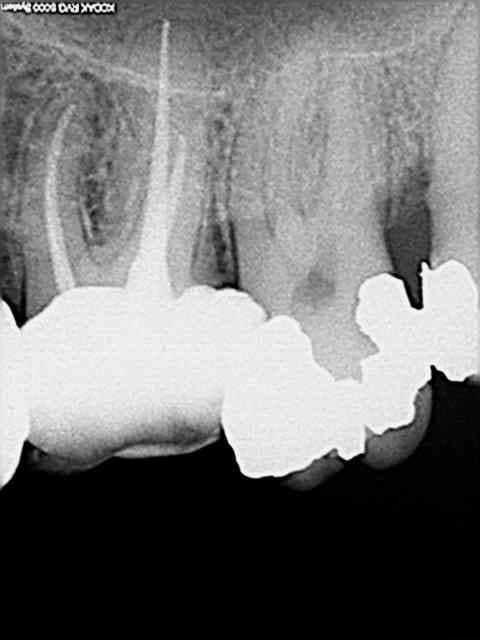

premier retraitement ce jour avec les protaper universal.

la prise en main est facile. On n'est pas dépaysé par rapport aux protaper classiques.

obturation par compactage avec les cones protaper.